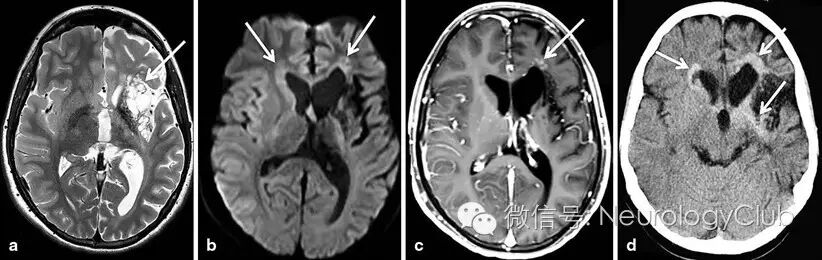

15岁高加索男孩,表现为数月缓慢进展的轻偏瘫,从右侧上肢开始,后累及下肢(肌力4级)。患者言语功能退化,包括清晰度和流畅度,学习成绩下降,反复夜间遗尿。患者在婴儿早期曾经历一次缺血性事件,长期遗留右侧面部瘫痪,尽管当时未行影像学检查。MRI提示多囊病灶伴左侧基底节区萎缩(图a)。前额叶白质和左侧基底节区可见FLAIR高信号,DWI高信号(图b),T1增强可见沿着胼胝体膝部和尾状核头的微小部分强化囊性变(图c)。CT平扫可见这些病灶呈高密度(图d)。左额部强化病灶行立体定向活检提示生殖细胞瘤。

(图:a:T2WI;b:DWI;c:T1增强;d:CT)